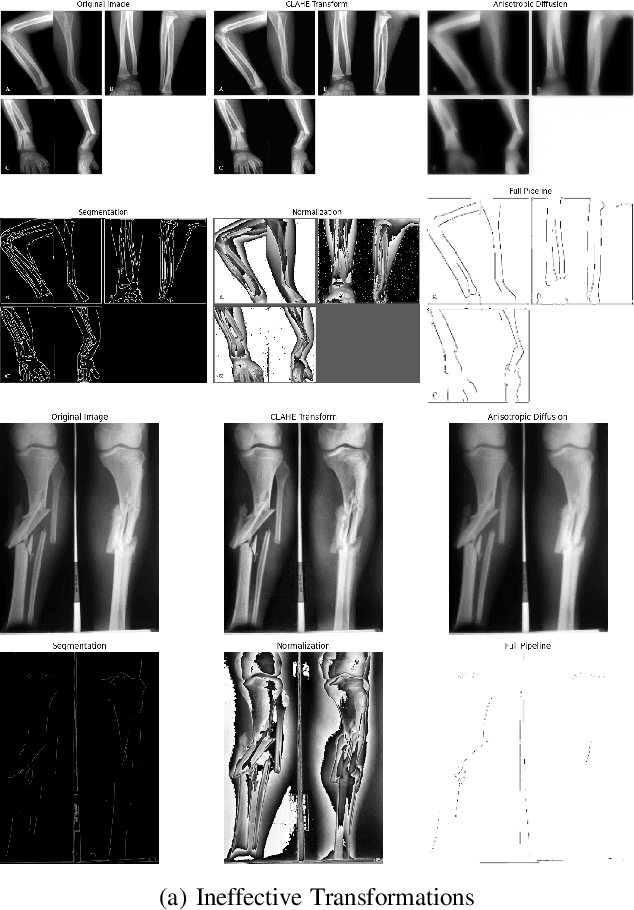

Abstract:The manual examination of X-ray images for fractures is a time-consuming process that is prone to human error. In this work, we introduce a robust yet simple training loop for the classification of fractures, which significantly outperforms existing methods. Our method achieves superior performance in less than ten epochs and utilizes the latest dataset to deliver the best-performing model for this task. We emphasize the importance of training deep learning models responsibly and efficiently, as well as the critical role of selecting high-quality datasets.